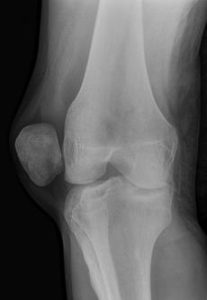

Диагностика осуществляется по рентгенограмме в 2 проекциях, но очень часто при укладке пациента на стол в рентген кабинете, наступает спонтанное вправление надколенника и зафиксировать его в положении вывиха не удается.